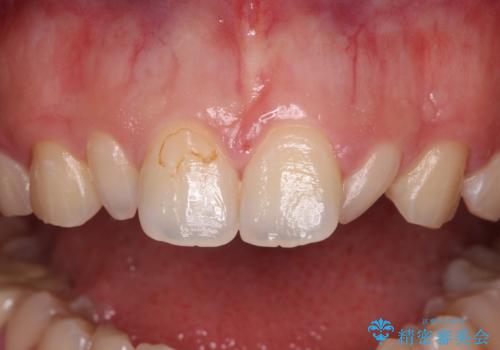

- 前歯の矮小歯と捻れや変色を気にして来院された患者様です。

結婚式が近いということもあり、前歯4本をオールセラミッククラウンにて補綴治療することとしました。